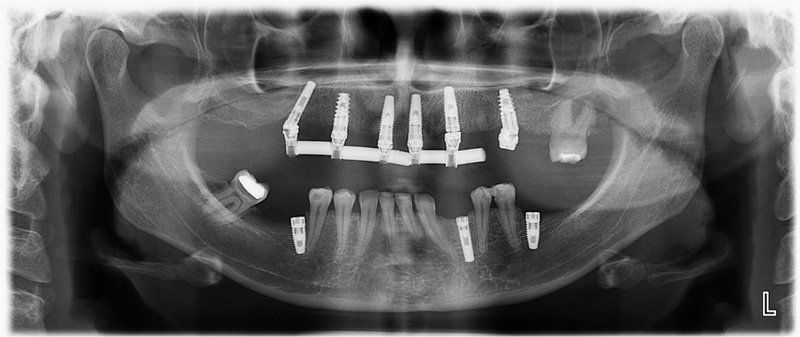

Los Implantes de Carga Inmediata son una solución práctica y definitiva para el desdentado total, es un tratamiento el cual una vez que se opera y se colocan los implantes, por un periodo entre 24 horas a 48 horas, se colocan los dientes en forma provisional, de esta forma el paciente queda con algo fijo mientras el implante se adhiere al hueso. Su principal ventaja radica en la reducción o eliminación del tiempo de espera entre la colocación del implante dental y la colocación de los dientes fijos.

Porque se hace en pabellones certificados por la Universidad de Chile. Son dependencias hechas única y exclusivamente para hacer intervención en sitios estériles. También se hace más cómodo y se pasa rápido el periodo de espera. Del momento en que se insertan los implantes debe transcurrir un período de tiempo de entre 4 a 6 meses si es en mandíbula o maxilar superiores respectivamente para que el tejido óseo cicatrice y logre integrarse a la superficie del implante